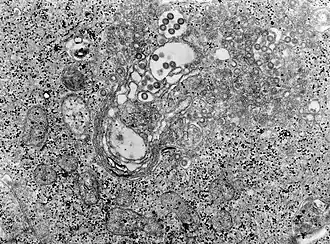

Het Riftdalkoortsvirus is een (-)ssRNA-virus, een zogeheten Phlebovirus een van de vijf genera uit de familie van de Bunyaviridae.[1]